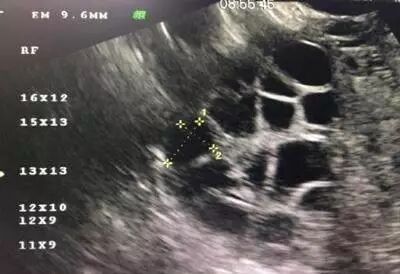

常用的监测排卵方法有基础体温测定(BBT)、阴道B超监测排卵、血清性激素测定等。

阴道B型超声动态监测卵泡的发育及排卵,是监测排卵最准确可靠的方法。通过阴道B超检查可以了解子宫及双侧附件(卵巢和输卵管)区的基本情况,测定卵巢内的基础卵泡计数,评估卵巢储备功能,动态监测排卵